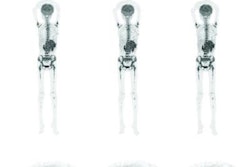

The researchers recruited 120 patients with NENs of all grades, 96 of whom had uPAR whole-body PET/CT scans (Biograph mCT, Siemens Healthineers) at Copenhagen University Hospital between November 2017 and June 2020. The majority of patients had small intestinal NENs (64%) and 90% had metastatic disease.

Image courtesy of the Journal of Nuclear Medicine.Tumors were defined as uPAR positive by two experts based on standardized uptake values (SUV) of the tracer in the lesions. Patients were followed for at least one year to determine their progression-free survival and overall survival.